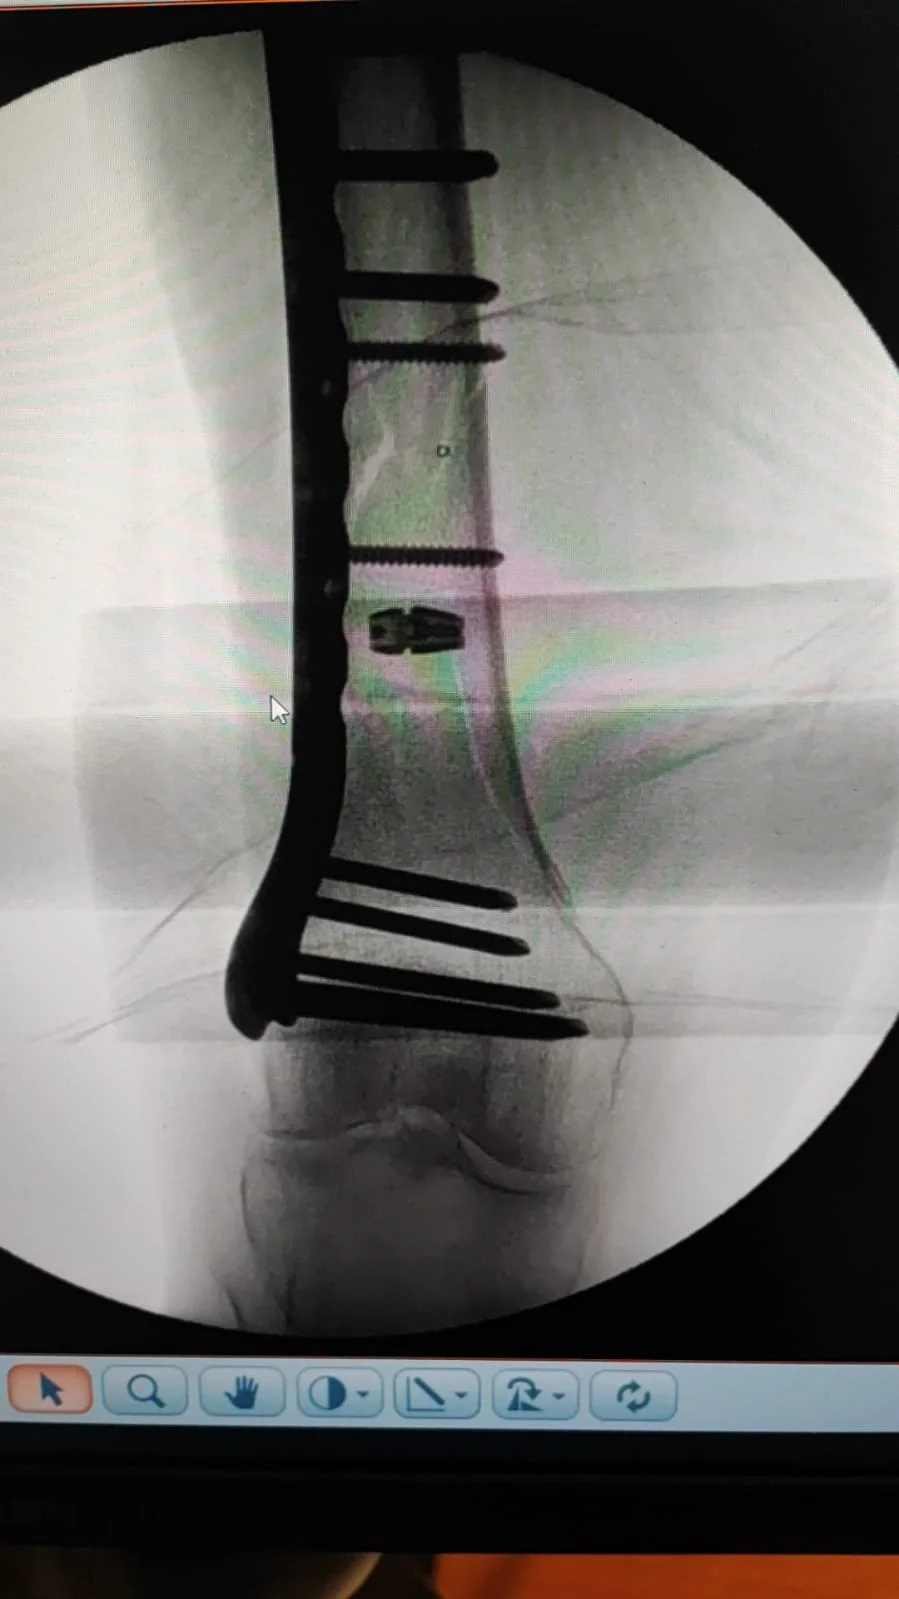

I stare at this blank page. Minutes pass. Sentences begin to form, and immediately unravel. I am looking for an entrance that will lead me to an outcome that makes sense, that allows me to accept this reality: the one that began on a sunny afternoon in Siena and ended with my right femur broken in 2 places, pain beyond measure, hours in the emergency room until an X-ray was taken and my leg then put in traction for a week before surgery on our Wedding Anniversary; surgery for which I was anaesthetized from the waist down but throughout which I remained conscious, while an 8″ titanium plate was attached to my femur with 8 screws!